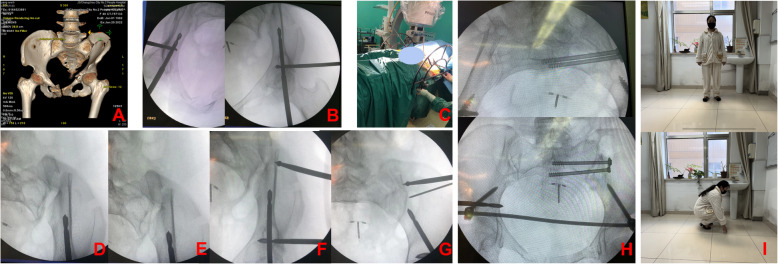

{"title":"Pelvic unlocking closed reduction device for treatment of severe traumas combined with pelvic fractures: a retrospective case series of 13 patients.","authors":"Jie Chen, Zhuangzhuang Zhang, Yiping Weng, Zhongjie Yu, Rongbin Sun, Yu Zhang","doi":"10.1186/s12893-025-03199-8","DOIUrl":null,"url":null,"abstract":"<p><strong>Background: </strong>Closed reduction and internal fixation is the key to early and minimally invasive treatment of pelvic fractures in patients with severe trauma. Although the pelvic unlocking closed reduction device has been promoted to a certain extent, the therapeutic effect and surgical strategies for treating severe trauma have not been clearly clarified. Our study was aimed to explore the therapeutic effect and surgical strategy skills of the pelvic unlocking closed reduction device in treating severe traumas combined with pelvic fractures.</p><p><strong>Methods: </strong>Data were retrospectively collected from 13 patients with severe traumas undergoing pelvic unlocking closed reduction for pelvic fractures in our hospital between July 2021 and December 2022. Seven males and six females aged 48(18~69), 46.4±16.7 years were involved. The operation time, times of fluoroscopy, and blood loss were recorded intraoperatively. Postoperative complications, and fracture healing time were recorded. The Matta and Majeed scales were used to evaluate fracture reduction and clinical efficacy respectively.</p><p><strong>Results: </strong>The time from injury to surgery was 7(4~14), 8.2±3 days. No wound infection, loosening or breakage of internal fixation, or loss of reduction occurred. The clinical healing time was 3(3~5), 3.5±0.7 months. Three cases suffered paresthesia on unilateral anterolateral thigh. According to the postoperative imaging Matta scores, 12 cases were excellent and 1 case was good, with an excellent rate of 12/13. At the last follow-up, the Majeed functional scores were excellent in all 13 cases.</p><p><strong>Conclusions: </strong>For patients with severe trauma combined with pelvic fracture, the pelvic unlocking and reduction device can be used for minimally invasive internal fixation at an early stage as long as their vital signs are stable. In this study, we summarized and advocated the 'turn-back order' reduction and internal fixation philosophy of 'posterior-ring unlocking - anterior ring to posterior ring reduction stabilization - posterior ring to anterior ring internal fixation placement' in pelvic closed reduction and internal fixation surgery.</p>","PeriodicalId":49229,"journal":{"name":"BMC Surgery","volume":"25 1","pages":"456"},"PeriodicalIF":1.8000,"publicationDate":"2025-10-07","publicationTypes":"Journal Article","fieldsOfStudy":null,"isOpenAccess":false,"openAccessPdf":"https://www.ncbi.nlm.nih.gov/pmc/articles/PMC12502416/pdf/","citationCount":"0","resultStr":null,"platform":"Semanticscholar","paperid":null,"PeriodicalName":"BMC Surgery","FirstCategoryId":"3","ListUrlMain":"https://doi.org/10.1186/s12893-025-03199-8","RegionNum":3,"RegionCategory":"医学","ArticlePicture":[],"TitleCN":null,"AbstractTextCN":null,"PMCID":null,"EPubDate":"","PubModel":"","JCR":"Q2","JCRName":"SURGERY","Score":null,"Total":0}

Results: The time from injury to surgery was 7(4~14), 8.2±3 days. No wound infection, loosening or breakage of internal fixation, or loss of reduction occurred. The clinical healing time was 3(3~5), 3.5±0.7 months. Three cases suffered paresthesia on unilateral anterolateral thigh. According to the postoperative imaging Matta scores, 12 cases were excellent and 1 case was good, with an excellent rate of 12/13. At the last follow-up, the Majeed functional scores were excellent in all 13 cases.

Conclusions: For patients with severe trauma combined with pelvic fracture, the pelvic unlocking and reduction device can be used for minimally invasive internal fixation at an early stage as long as their vital signs are stable. In this study, we summarized and advocated the 'turn-back order' reduction and internal fixation philosophy of 'posterior-ring unlocking - anterior ring to posterior ring reduction stabilization - posterior ring to anterior ring internal fixation placement' in pelvic closed reduction and internal fixation surgery.